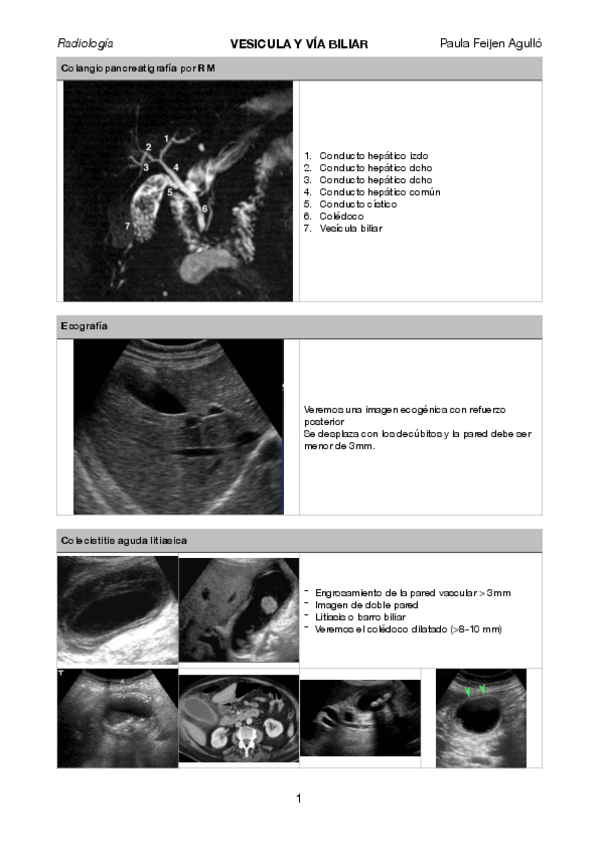

pancreas.pdf

via-biliar.pdf